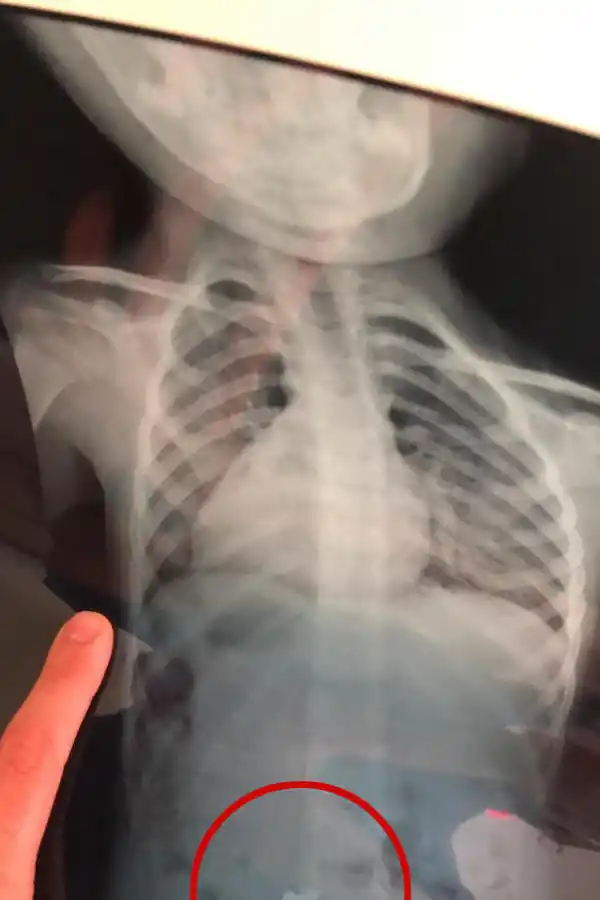

No habían notado nada hasta que Maitena empezó a toser. “¿Qué pasa? ¿Estás bien?”, le preguntó su papá. La pequeña de tres años dijo que sí, y siguió jugando. El padre no se quedó tranquilo. Unos minutos antes había visto que tenía entre sus chucherías una mamadera con tres tornillos adentro. Inmediatamente la buscó y ahí se dio cuenta. Faltaba uno. En la sala de urgencias del Hospital de Niños una radiografía confirmó las sospechas: ahí estaba el objeto de metal; ya había pasado el esófago y estaba ingresando al estómago.

SUSTO. La radiografía de Maitena mostró que se había tragado un tornillo. Por suerte pasó rápido el esófago y luego lo despidió.